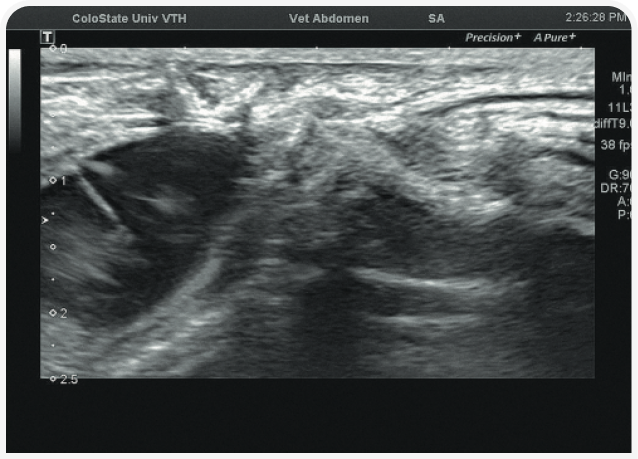

Решающее значение для диагностики и лечения в этом случае будет иметь ультразвуковое исследование органов брюшной полости (Рисунок 6). Диагностику триадита у кошек облегчают визуализация поджелудочной железы и определение толщины/архитектоники стенки кишечника; изменения в паренхиме печени по-прежнему остаются неспецифичными, но изменения в желчном пузыре, скорее всего, помогут установить диагноз. При нейтрофильном холангите у кошки результаты визуализации желчных путей могут оказаться нормальными, но во многих случаях стенка желчного пузыря будет утолщенной и неровной, даже зубчатой (Рисунок 7) (22). Возможны осадок (Рисунок 8) или наличие камней в желчном пузыре, поэтому желчевыводящие пути важно просмотреть до двенадцатиперстной кишки, чтобы исключить внепеченочную окклюзию желчных протоков. Во многих случаях общий желчный проток оказывается перекрыт. Возможен асцит, и в этом случае оправдано проведение аспирации и анализа состава жидкости.

Аспирация содержимого желчного пузыря (чрескожный холецистоцентез под контролем ультразвукового исследования) для цитологического и культурального исследования чаще всего позволяет поставить диагноз и подобрать лечение (Рисунок 9) (23). Если желчный пузырь при визуализации выглядит патологически (например, толщина стенки >1 мм, контур стенки неровный или зубчатый или выраженное гиперэхогенное содержимое (осадок; Рисунок 10), результаты цитологического исследования и бактериального посева, скорее всего, также будут отклоняться от нормы (22,24). Обратите внимание, что при аспирации существует риск разрыва стенки желчного пузыря и/или утечки содержимого с развитием желчного перитонита, но под контролем опытного специалиста УЗИ и при спокойном поведении/седации пациента проблемы возникают редко. Тем не менее если стенка желчного пузыря выглядит эмфизематозной, риск значительно возрастает и вместо аспирации следует рассмотреть возможность хирургического удаления или пробное лечение.